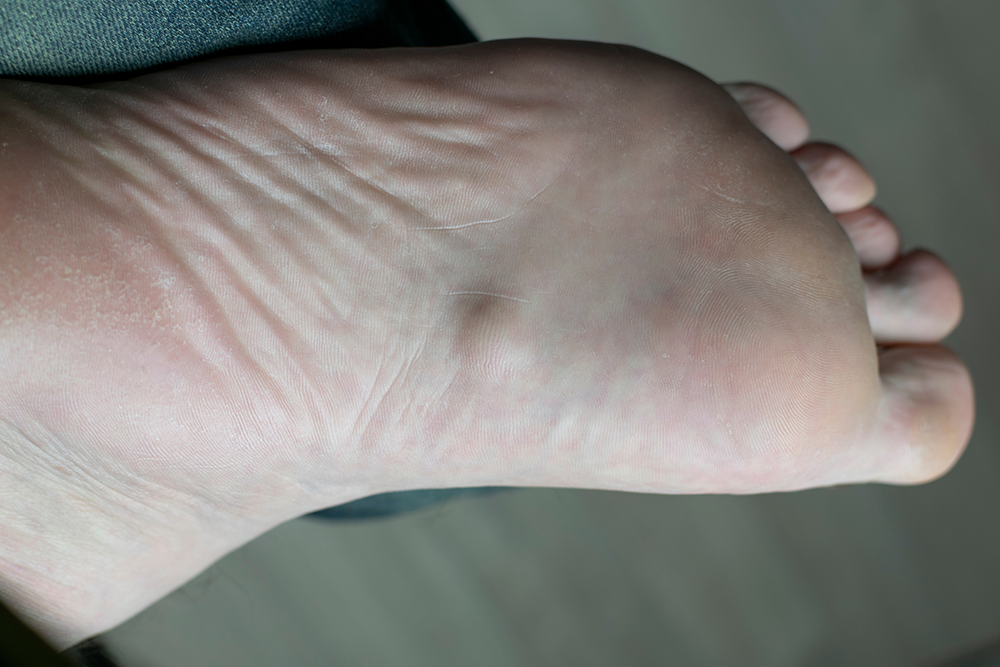

We provide complete foot and ankle care for patients of all ages, including injury treatment, pain relief, diabetic foot management, and preventive care. Our goal is to restore comfort, mobility, and long-term health through personalized treatment plans and advanced diagnostics. Explore the services below to see how we can help you stay active and pain free.